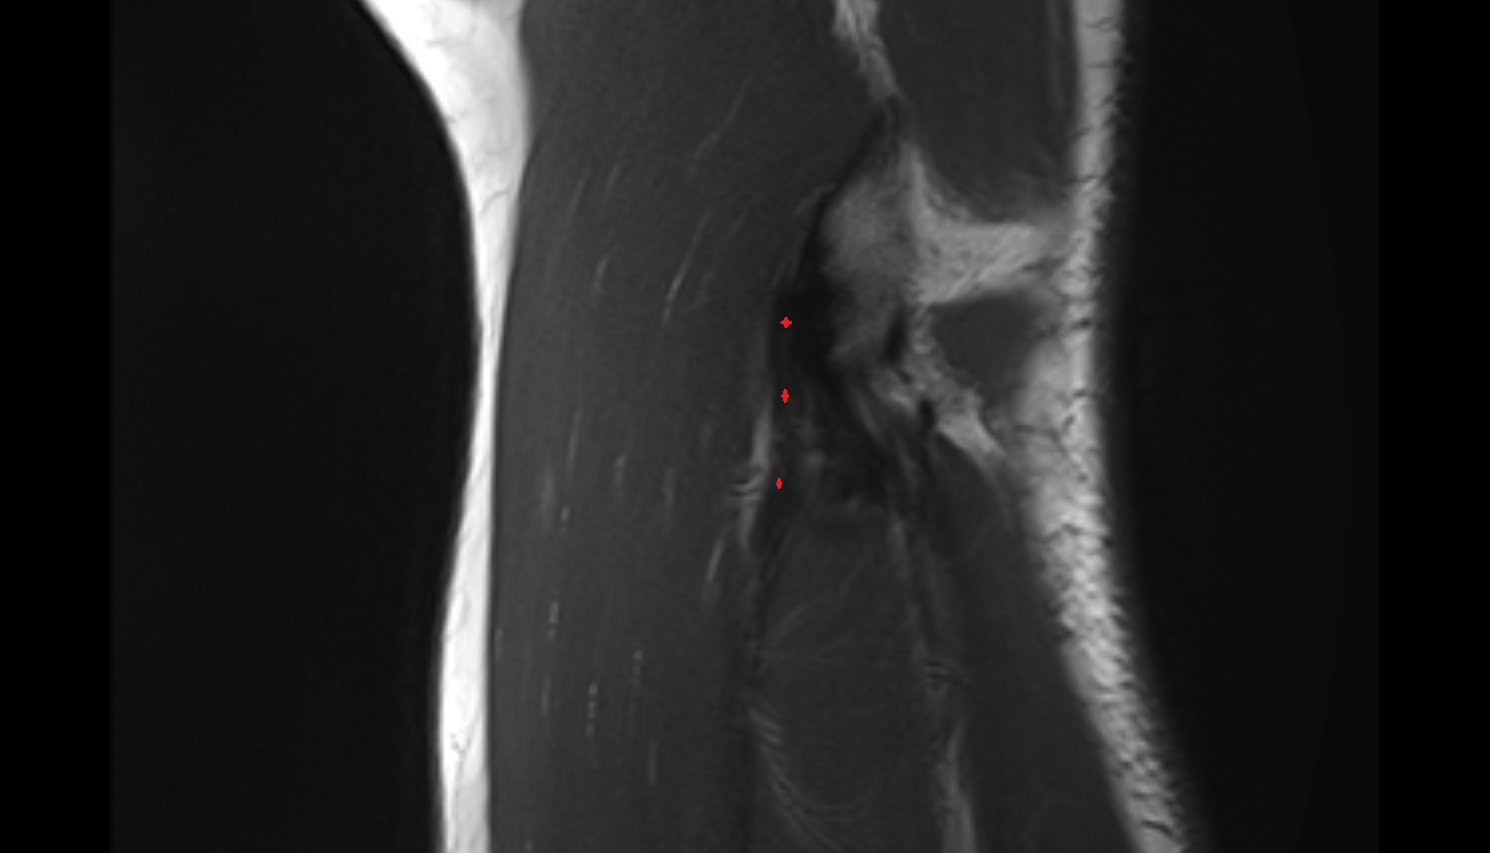

- Anterior cruciate ligament